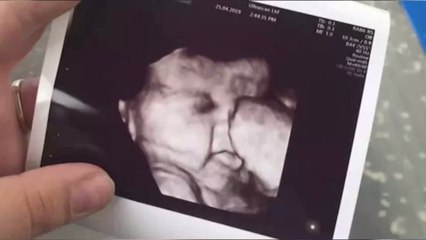

His mother once saw Superstar Rajinikanth in TV while she was pregnant